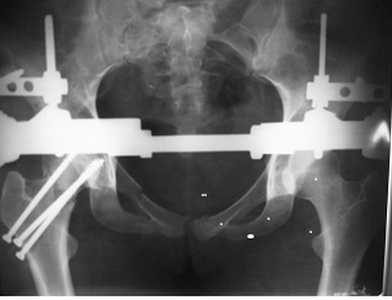

У нас был такой случай, прооперировал на 3 сутки. Результат полное выздоровление.